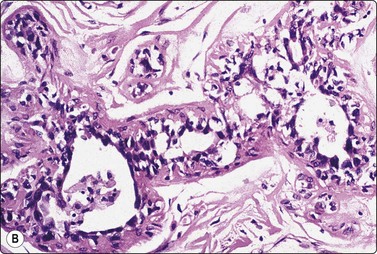

Breast tissue in pregnancy and lactation (Fig. 7.8)

image image image

Fig. 7.8 Lactating breast

Dispersed acinar cells with abundant pale and fragile cytoplasm, rounded nuclei and prominent central nucleoli; background of lipid secretions (A, MGG, HP; B, H & E, HP oil); (C) Corresponding tissue section (H&E, IP).

Criteria for diagnosis

Cellular smears,

Poorly cohesive, mainly dispersed epithelial cells of acinar type,

Cells have abundant fragile cytoplasm with secretory vacuoles and frayed borders,

Rounded vesicular nuclei and central nucleoli,

Dirty background due to lipid secretion and stripped nuclei with prominent nucleoli,

Single bipolar nuclei difficult to find.

FNB is very useful in reducing surgical intervention to a minimum during pregnancy and lactation. The pattern seen in FNB smears of ‘lumps’ in a pregnant or lactating breast can be problematic to inexperienced eyes and cause concern for malignancy.93,94 Smears are usually cellular. The cells are enlarged and arranged in loose groups or singly. The cells have an abundant fragile cytoplasm, vacuolated and finely granular. Nuclei are round, central, larger than the usual ductular cells, and have distinct small nucleoli (Fig. 7.8B). Some epithelial nuclei are stripped of cytoplasm. Single naked bipolar/oval nuclei are difficult to find. The background of abundant milky secretion with numerous lipid droplets seen as vacuoles is characteristic of actively secreting breast tissue and is the main clue to the diagnosis (Fig. 7.8A).